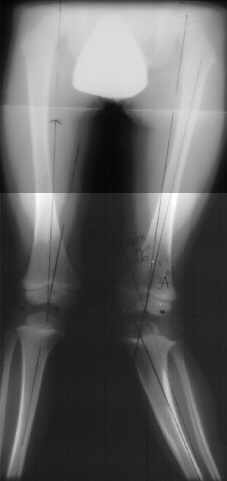

the left (image1). X-rays were repeated at 16 Months post fracture(image

2), the mechanical axis from the x-ray was measured at 8 degrees

on the right and 26 degrees on the left and the left femoral tibio

angle was 34 degrees. At this time the child was experiencing

significant pain and the inability to ambulate. He is now 4.5

years old.